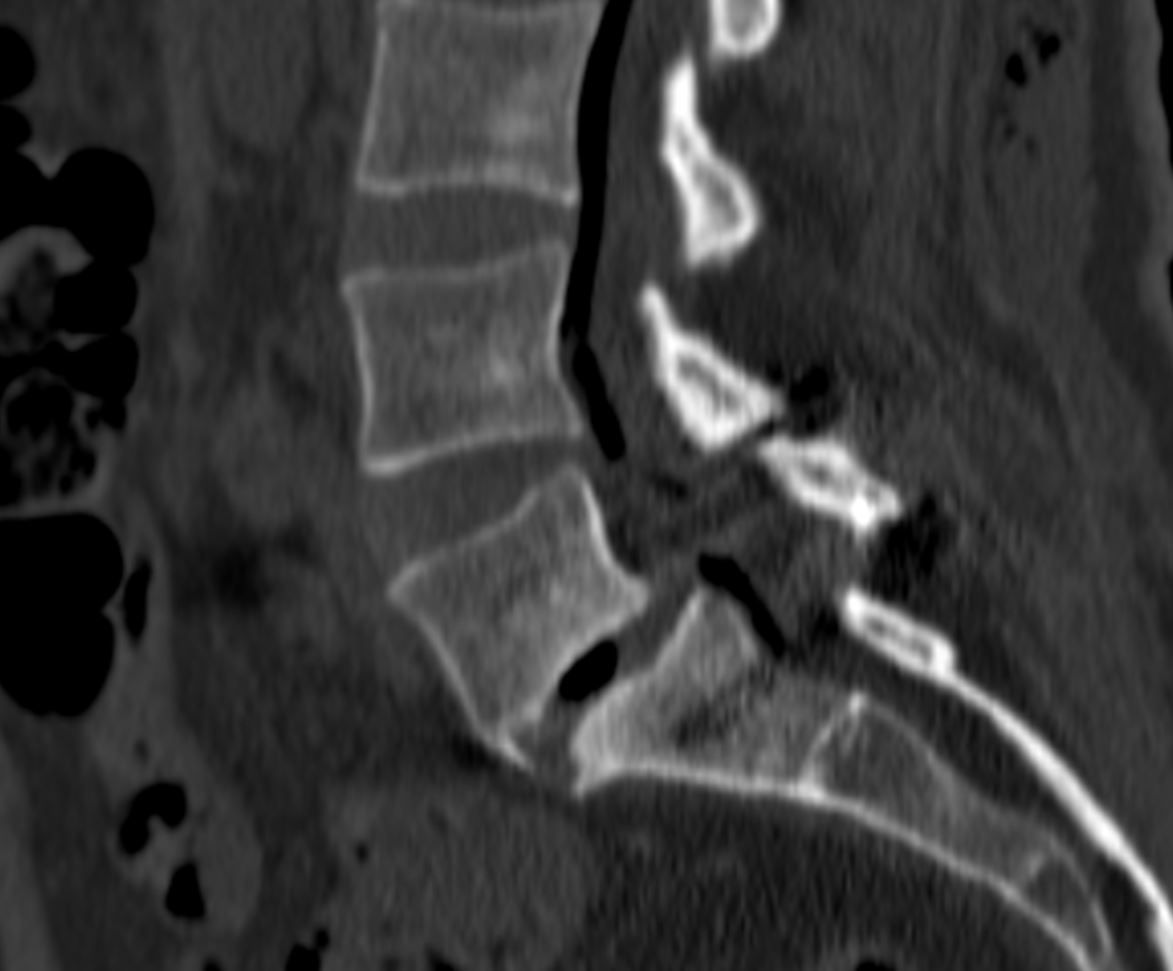

Ο απεικονιστικός έλεγχος ανέδειξε σπονδυλολίσθηση 2ου βαθμού σε έδαφος σπονδυλόλυσης στο ύψος Ο5-Ι1.

Διενεργήθη διαδερμική (ελάχιστα επεμβατική) σπονδυλοδεσία στο επίπεδο Ο5-Ι1

Η διαδερμική σπονδυλοδεσία μπορεί να χρησιμοποιηθεί ακόμα και οταν υπάρχει σπονδυλολίσθηση, αρκεί να μην είναι μεγάλου βαθμού. Σημαντικό είναι να τοποθετηθεί αρκετό οστικό μόσχευμα (πχ. στο μεσοσπονδύλιο διάστημα) προκειμένω να επιτευχθεί η «συνένωση» των σπονδύλων. Έτσι, επιτυγχάνεται ανάταξη της ολίσθησης και αποκατάσταση της σωστής ανατομίας της σπονδυλικής στήλης αλλά και ο ασθενής επωφελείται απο τα πλεονεκτήματα των ελάχιστα επεμβατικών τεχνικών.